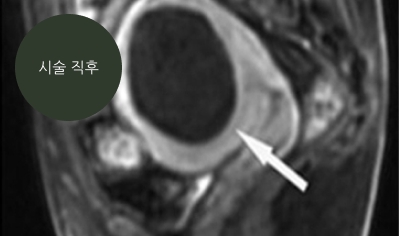

하이푸 시술 이후 근종 부위의 혈류가 감소하여 검게 보이는 것은

고강도초음파 에너지로 주변 조직 손상 없이 근종 절제(ablation)가 이루어진 것을 의미합니다.

하얀 화살표, 검게 보이는 타원형으로시술 후(6개월)